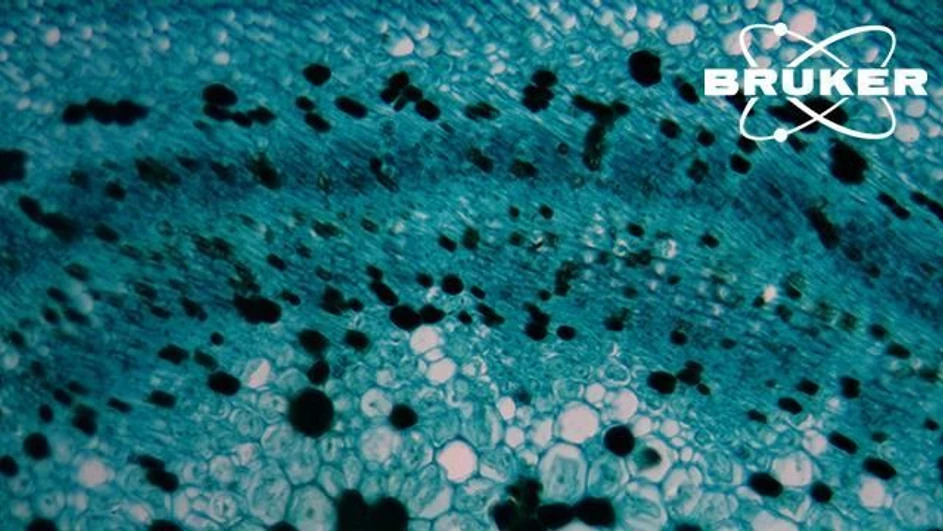

When reconstructing and analyzing the tumor–immune microenvironment (TIME), exploring the spatial context of the tumor at single-cell resolution can bring new insights into the cell–cell or cell–extracellular matrix interactions.

Mapping the TIME in three dimensions offers researchers the opportunity to probe deeper into spatial cell heterogeneity in tumors and understand the impact of the TIME on cancer growth and evolution.